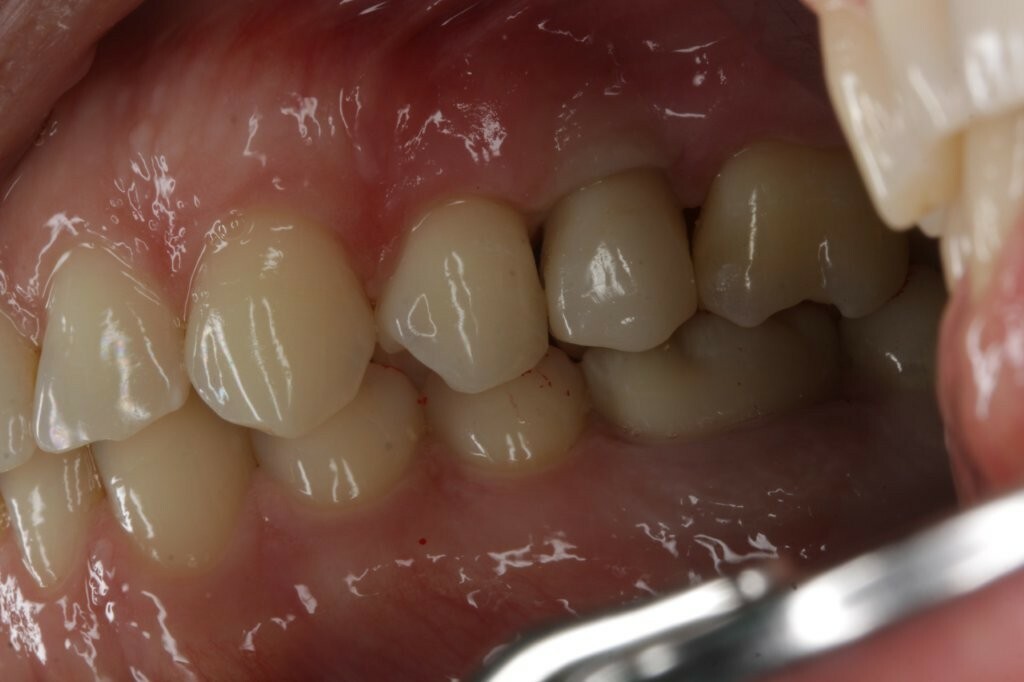

Ein Patient mit einem gepflegten Gebiss in eugnather Verzahnung (Abb. 1) stellte sich aufgrund einer Kronen-Wurzelfraktur an Zahn 25 in der Praxis vor. Die Untersuchung ergab, dass der Zahn aufgrund einer Fraktur des palatinalen Höckers mit subkrestalem Frakturverlauf (Abb. 2) nicht erhaltungswürdig war.